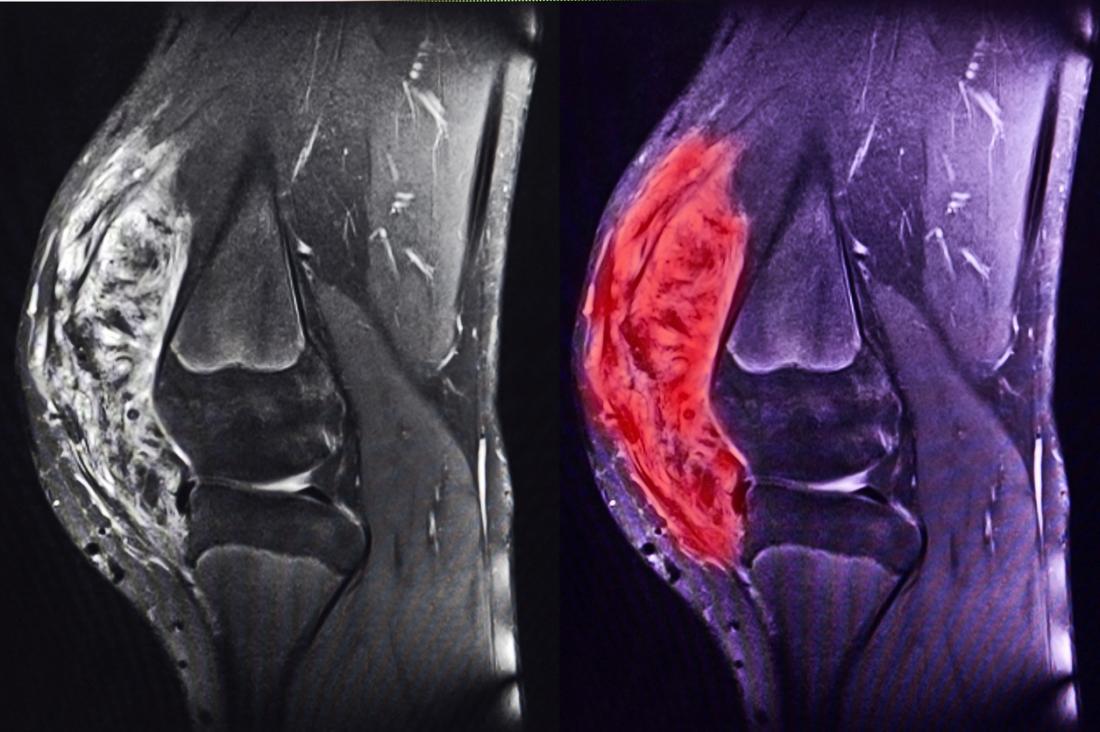

Для диагностики саркомы колена используются методы визуализации, такие как рентген, МРТ и КТ, а также биопсия для подтверждения злокачественного характера образования. Лечение саркомы колена зависит от стадии заболевания и может включать хирургическое вмешательство, химиотерапию и радиотерапию. Врачи подчеркивают важность комплексного подхода и индивидуального выбора методов лечения для каждого пациента, что значительно повышает шансы на успешное выздоровление.

При появлении симптомов, указывающих на патологию, пациенту следует обратиться к онкологу. После всестороннего обследования врач назначит соответствующее лечение. Для определения характера опухоли могут быть рекомендованы следующие процедуры:

- компьютерная томография (КТ);

- магнитно-резонансная томография (МРТ).

Для точной диагностики может потребоваться биопсия, которая уточнит гистологический тип новообразования.